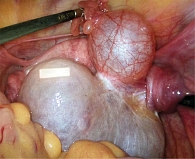

Рис. 1. УЗИ ОМТ пациентки А., 11 лет: объемное образование левых придатков матки, старый перекрут левых придатков матки

При пальпации в области живота – болезненность над лоном слева и опухолевидное образование. Данные ультразвукового исследования (УЗИ): образование в проекции левого яичника размером 4,7 × 3,8 × 4,8 см с неоднородной структурой и четкими контурами, старый перекрут левых придатков матки (рис. 1). Выявлено также небольшое количество свободной жидкости в полости малого таза (0,8 см). Заключение: эхопризнаки образования левого яичника, предположительно кисты желтого тела.

Пациентку направили на консультацию в Российскую детскую клиническую больницу (РДКБ) – филиал Российского национального исследовательского медицинского университета (РНИМУ) им. Н.И. Пирогова, где было принято решение о госпитализации. Данные осмотра: оволосение по женскому типу, слизистая оболочка вульвы розового цвета, клитор не гипертрофирован, выделения светлые, слизистые. При ректоабдоминальном обследовании выявлено тугоэластическое образование в области левых придатков диаметром 8 см, безболезненное при пальпации. Анализы крови и мочи в пределах возрастных норм. УЗИ ОМТ: матка в anteflexio размером 40 × 21 × 34 мм, шейка – 29 × 22 мм, структура миометрия однородная. Размер правого яичника 33 × 22 × 23 мм. Со стороны левого яичника визуализируется округлое образование неоднородной структуры размером 92 × 70 × 61 мм. Заключение: доброкачественное новообразование левого яичника; нельзя исключить старый перекрут левых придатков матки.